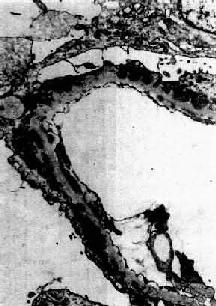

图12-19 膜性肾小球肾炎 电镜下见肾小球毛细血管基底膜增厚,电子致密沉积物被增生的基底膜包围并埋藏于基底膜内 肾小球毛细血管损伤,通透性显著增加,大量蛋白由肾小球滤过进入肾小管,部分被肾小管再吸收。近曲小管上皮细胞浊肿,胞浆内常有玻璃样变颗粒和大量脂肪空泡。晚期随肾小球病变加重,肾小管也萎缩。间质纤维组织增生,炎性细胞浸润较少。 肉眼观,早期可见肾肿胀,体积增大,色苍白。切面皮质明显增宽,髓质无特殊变化。晚期,肾体积缩小,表面呈细颗粒状。 【临床病理联系】 膜性肾小球肾炎是引起肾综合征最常见的原因之一。成人肾病综合征由膜性肾小球肾炎引起者约占40%,小儿仅占5%。膜性肾小球肾炎时,肾小球基底膜严重损伤,通透性显著增加,大量蛋白包括大分子蛋白都可由肾小球滤过引起严重的非选择性蛋白尿。由于大量蛋白由尿中排出,血浆蛋白降低,引起低蛋白血症,血浆胶体渗透压降低,血管内液体渗入组织间隙,引起水肿。同时血容量减少,肾小球血流量和肾小球滤过减少,醛固酮和抗利尿激素分泌增加,引起水钠潴留,进一步加重水肿。因此水肿很严重,往往为全身性,以眼睑和身体下垂部分最明显,严重者并可有胸水和腹水。 高脂血症的原因还不很清楚,可能由于低蛋白血症刺激肝合成各种血浆蛋白包括脂蛋白增多,因此病人有高脂血症和高胆固醇血症。由于血脂过高,血浆内的脂蛋白也可由肾小球滤过,引起脂尿症。 膜性肾小球肾炎时,肾小球内无明显增生和炎症现象。早期,毛细血管不狭窄,血流通畅,故血尿不多见,血压不高,无明显氮质血症。晚期,毛细血管阻塞,肾小球硬化,可引起高血压和肾功能衰竭。 【结局】 膜性肾小球肾炎起病缓慢,病程较长。病变轻者,症状可消退或部分缓解。多数则反复发作,对皮质激素治疗效果不显著。发展到晚期,大量肾单位纤维化、硬化,可导致肾功能衰竭和尿毒症。